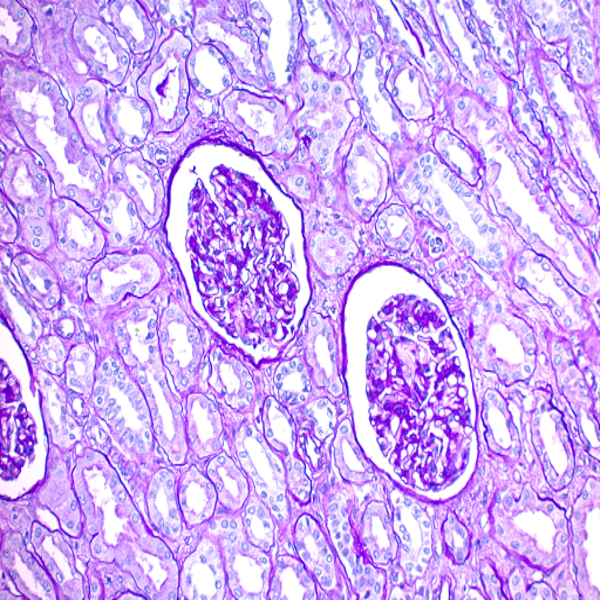

- Preparation of paraffin and frozen tissue sections in different sizes

- General and specialized tissue and cell staining

Histological methods includes sample processing in the pathology laboratory, preparation of the slide and its examination under a microscope, sample fixation, molding, microtome cutting, staining and assembly of the slides.